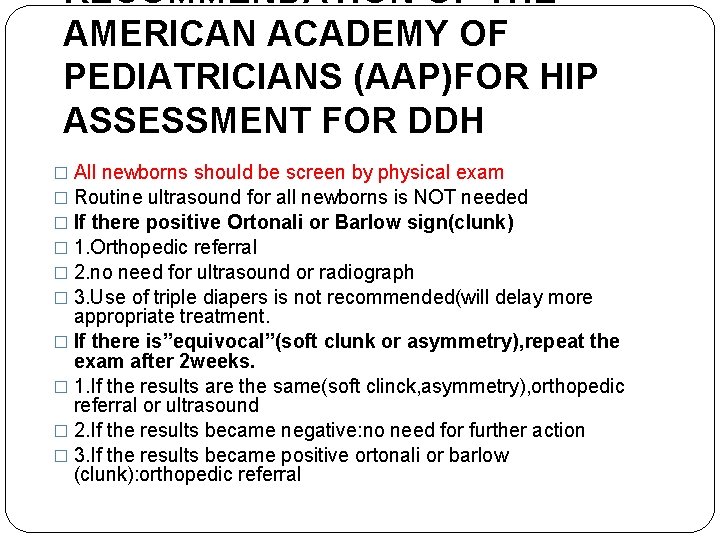

RECOMMENDATION OF THE AMERICAN ACADEMY OF PEDIATRICIANS (AAP)FOR HIP ASSESSMENT FOR DDH � All newborns should be screen by physical exam � Routine ultrasound for all newborns is NOT needed � If there positive Ortonali or Barlow sign(clunk) � 1. Orthopedic referral � 2. no need for ultrasound or radiograph � 3. Use of triple diapers is not recommended(will delay more appropriate treatment. � If there is”equivocal”(soft clunk or asymmetry), repeat the exam after 2 weeks. � 1. If the results are the same(soft clinck, asymmetry), orthopedic referral or ultrasound � 2. If the results became negative: no need for further action � 3. If the results became positive ortonali or barlow (clunk): orthopedic referral